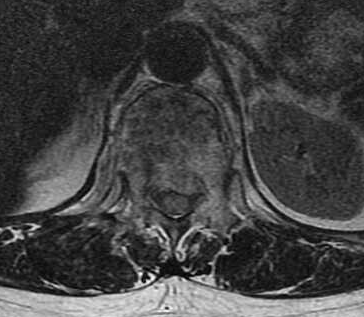

▲术前胸腰段MR提示:第12节胸椎和第1、3、4节腰椎压缩改变伴骨髓水肿,其中第12节胸椎压缩严重,椎管占位明显,脊髓受压变形。